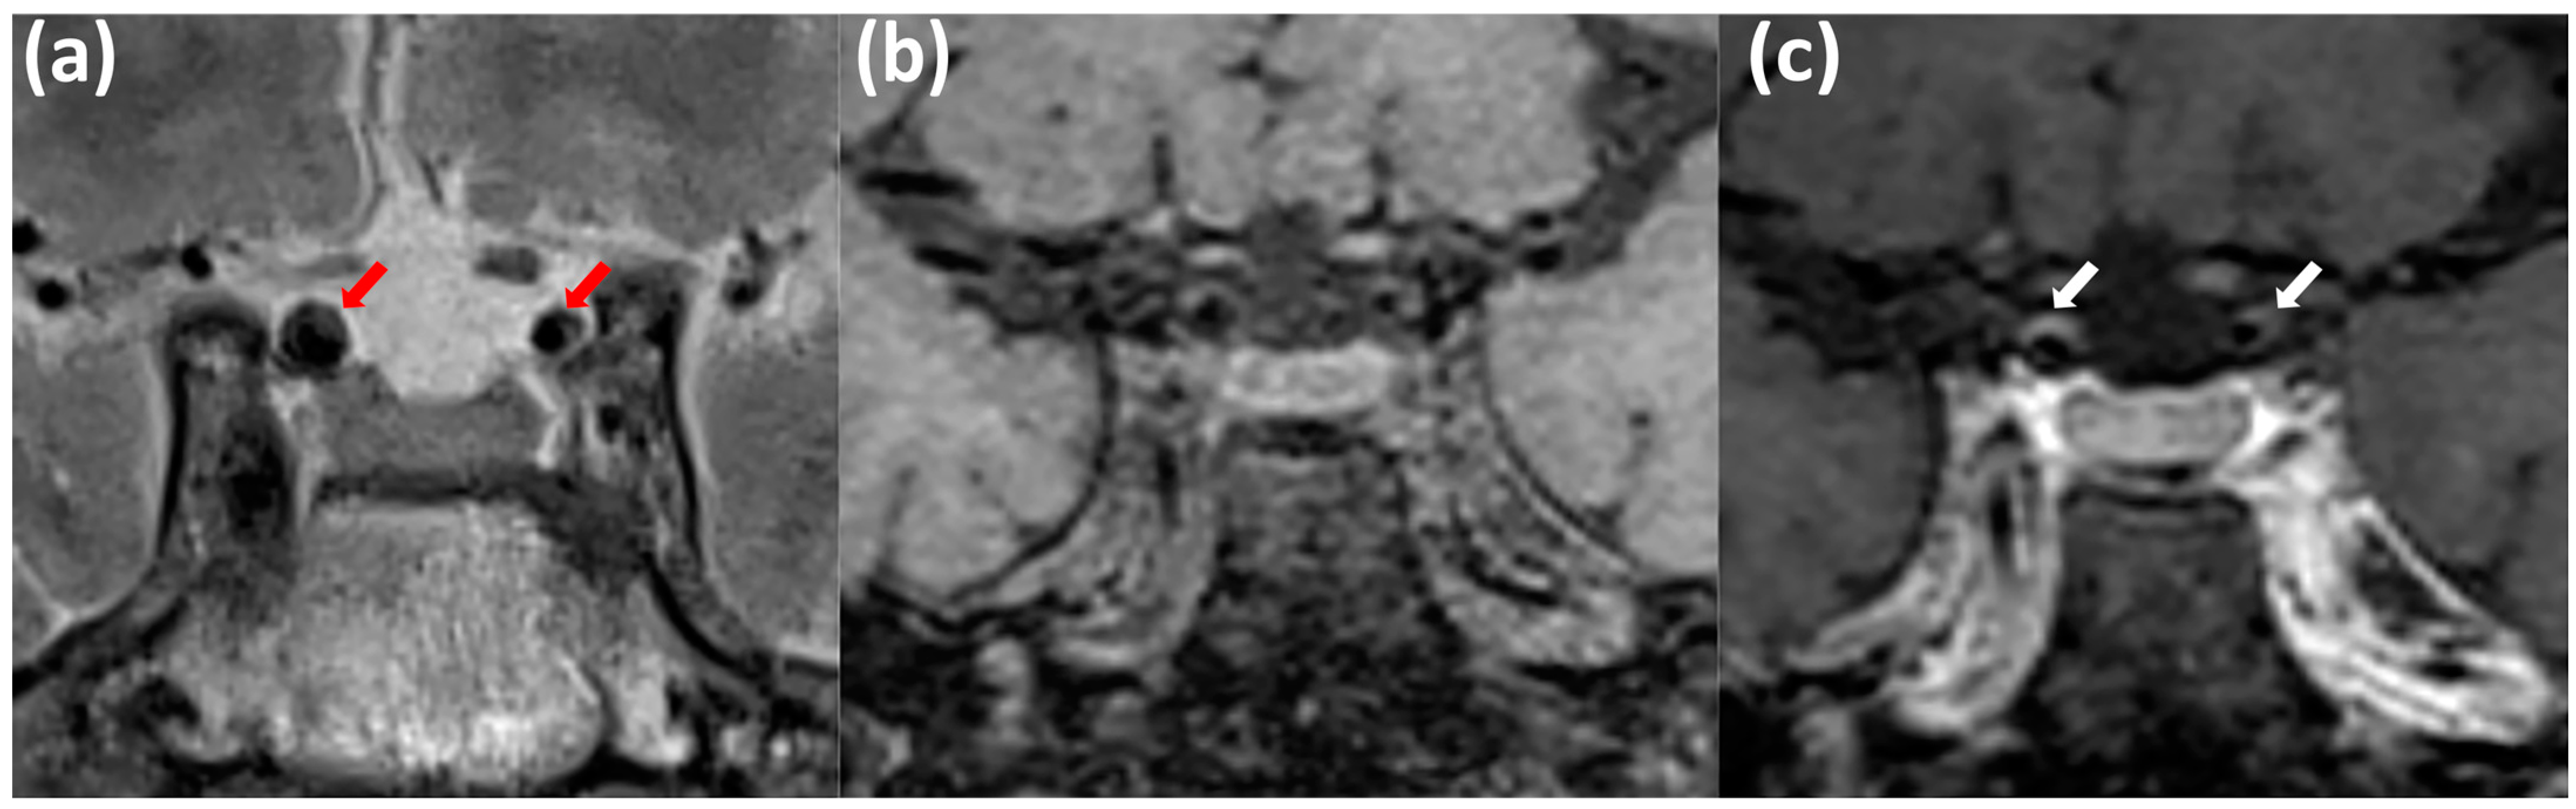

- Kang, D.W.; Kim, D.Y.; Kim, J.; Baik, S.H.; Jung, C.; Singh, N.; Song, J.W.; Bae, H.-J.; Kim, B.J. Emerging Concept of Intracranial Arterial Diseases: The Role of High Resolution Vessel Wall MRI. J. Stroke 2024, 26, 26–40. [Google Scholar] [CrossRef] [PubMed]